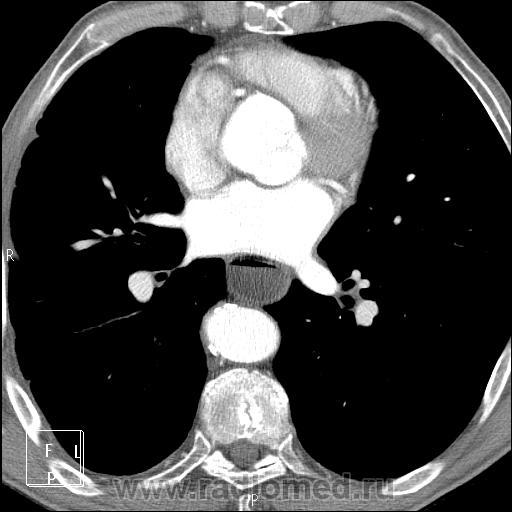

Протокол болюса подгоняла под все выявленные изменения, артериальная фаза:

очаг в правом легком:

Пищевод и зона анастомоза:

В области анастомоза накопление контраста до 100 ед.Н, в более проксимальных отделах пищевода накопление стенкой нормальное, до 45 ед.Н.